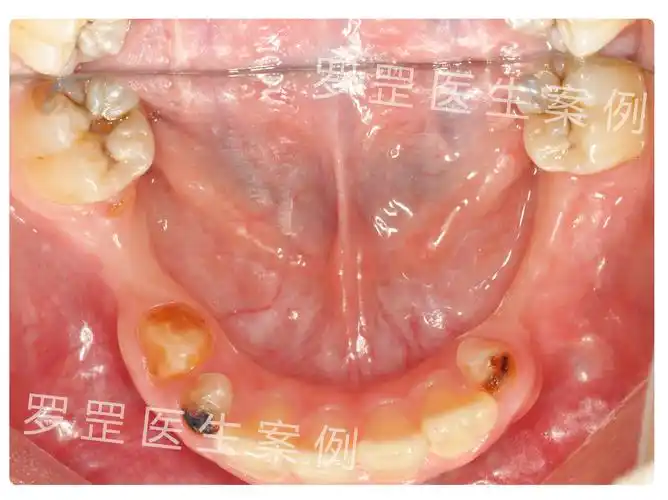

乳牙坏了不用管?未及时治疗,4岁男童一口牙几乎烂光

详解乳牙过早丢失的主要原因及处理方法

乳牙缺失后最重要的事先检查要不要做缺隙保持器